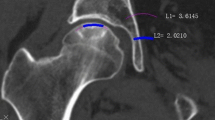

We collected data of 900 consecutive patients (634 males) with bilateral (428) or unilateral non-traumatic osteonecrosis diagnosed before collapse (at stage I or stage II). The follow-up was average five years (3 to 8 years). A total of 50 variables related to the osteonecrosis were included in the study. The osteonecroses were randomly divided into a training set (80%) and a validation set (20%) with a similar percentage of hips with collapse in the two groups. Machine learning (ML) algorithms were trained with the selected variables. Performance was evaluated and the different factors (variables) for collapse were ranked with Shapley values. The primary outcome was prediction of occurrence of collapse from automated inventory systems.

In this series of patients, the accuracy with machine learning for predicting collapse within three years follow-up was 81.2%. Accuracies for predicting collapse within six to 12-24 months were 54.2%, 67.3%, and 71.2%, respectively, demonstrating that the accuracy is lower for a prevision in the short term than for the mid-term. Despite none of the risk-factors alone achieving statistical significance for prediction, the system allowed ranking the different variables for risk of collapse. The highest risk factors for collapse were sickle cell disease, liver, and cardiac transplantation treated with corticosteroids, osteonecrosis volume > 50% of the femoral head. Cancer (such as leukemia), alcohol abuse, lupus erythematosus, Crohn’s disease, pemphigus vulgaris treated with corticosteroids, and osteonecrosis volume between 40 and 50% were medium risk factors for collapse. Familial cluster of collapse, HIV infection, chronic renal failure, nephrotic syndrome, and renal transplantation, when treated with corticosteroids, stage II, osteonecrosis volume between 30 and 40%, chemotherapy, hip pain with VAS > 6, and collapse progression on the contralateral side, were also significant but lowest risk factors. A heat map is proposed to illustrate the ranking of the combinations of the different variables. The highest risk of collapse is obtained with association of various risks factors.

Hernigou P, Lambotte JC (2001) Volumetric analysis of osteonecrosis of the femur. Anatomical correlation using MRI. J Bone Joint Surg Br 83:672–5